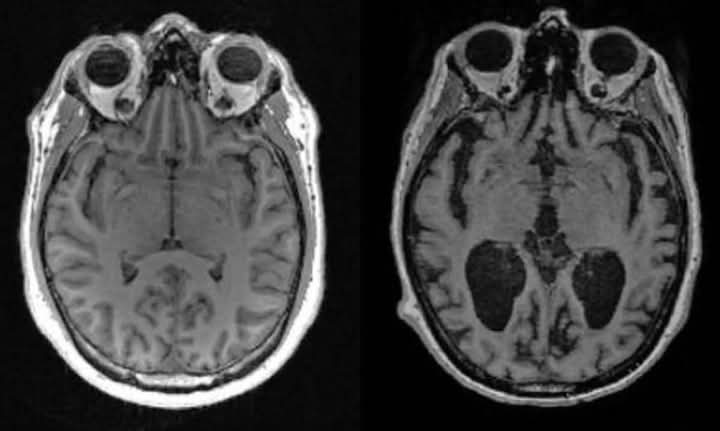

Científicos de la Facultad de Medicina de Harvard descubrieron que la pérdida de litio en el cerebro humano es uno de los primeros cambios que conducen al Alzheimer, mientras que en ratones, una depleción similar de litio aceleraba el deterioro de la memoria.

En algunos casos se detectó un nivel reducido de litio debido a la absorción deficiente del metal y a su unión a las placas amiloides, conocidas como señales inequívocas del Alzheimer.

El análisis reveló que el litio era el único metal con niveles marcadamente diferentes entre los grupos, que además parecían cambiar en las fases más tempranas de la pérdida de memoria.